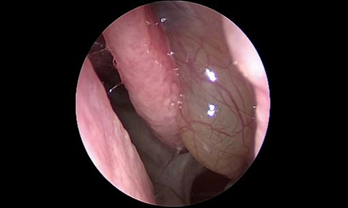

- Phát hiện sớm các trường hợp polyp mũi xoang, ung thư vòm họng qua nội soi.

Phẫu thuật nội soi chức năng xoang (Functional Endoscopic Sinus Surgery-FESS) giúp trả lại hệ thống xoang thông thoáng với kỹ thuật không đặt bấc mũi.

- Phẫu thuật nội soi mũi xoang với hệ thống định vị trong lúc mổ (Navigation) cho phép bác sĩ tiếp cận trực tiếp đến các vùng mũi xoang bị viêm, gia tăng khả năng quan sát các mốc giải phẫu trong hốc mũi để đánh giá một cách chính xác các bệnh lý sâu trong hốc mũi.

- Trên cơ sở đó, bác sĩ có thể dễ dàng thao tác loại bỏ sạch các tác nhân gây viêm và mủ mà vẫn bảo tồn tối đa niêm mạc lành và hạn chế nạo bỏ niêm mạc triệt để, tối ưu lưu thông không khí trong hệ thống xoang.

- Hỗ trợ đắc lực cho các ca phẫu thuật xoang tại bệnh viện SIS Cần Thơ là hệ thống nội soi Karl Storz cùng máy chụp cắt lớp thế hệ mới nhất CT photon, cho phép phát hiện những tổn thương nhỏ tại hốc mũi xoang. Bên cạnh đó, máy khoan cắt hút mô liên tục đa chức năng Nouvag của Thụy Sĩ giúp tăng độ chính xác, giảm tổn thương niêm mạc, rút ngắn thời gian phẫu thuật.